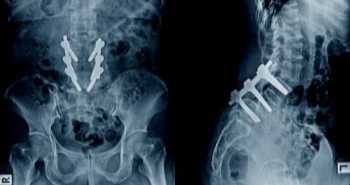

Цель исследования состояла в разработке инструмента для оценки риска, который можно использовать для составления прогнозов и количественной оценки вероятности первичного патологического перелома и связанных с ним исходов в виде последующего перелома и смертельного исхода на основе модели со многими состояниями.

В исследование были включены данные 8965 пациентов в возрасте 60 лет и старше из двух схожих проспективных популяционных когортных исследований DOES (Dubbo Osteoporosis Epidemiology Study) и CaMos (Canadian Multicentre Osteoporosis Study). Случаи впервые выявленных переломов были отобраны по результатам рентгенографии и опросников. Информация о смертельных исходах была получена от родственников или из некрологов.

В модели прогнозирования учитываются такие факторы, как возраст, минеральная плотность костной ткани (МПКТ), случаи падения за предыдущие 12 месяцев, пол, предшествующие переломы в возрасте старше 50 лет, онкологические заболевания, сердечно-сосудистые заболевания, артериальная гипертензия, хронические заболевания легких и сахарный диабет в анамнезе.

Данная модель позволяла точно спрогнозировать развитие патологических переломов в течение 11 лет периода наблюдения, смертельный исход после перелома в течение 9 лет, в пределах от 7 лет после перелома бедра до 15 лет в случае других переломов.

У пациентов пожилого возраста инструмент оценки риска позволяет точно спрогнозировать развитие патологических переломов и смертельный исход.